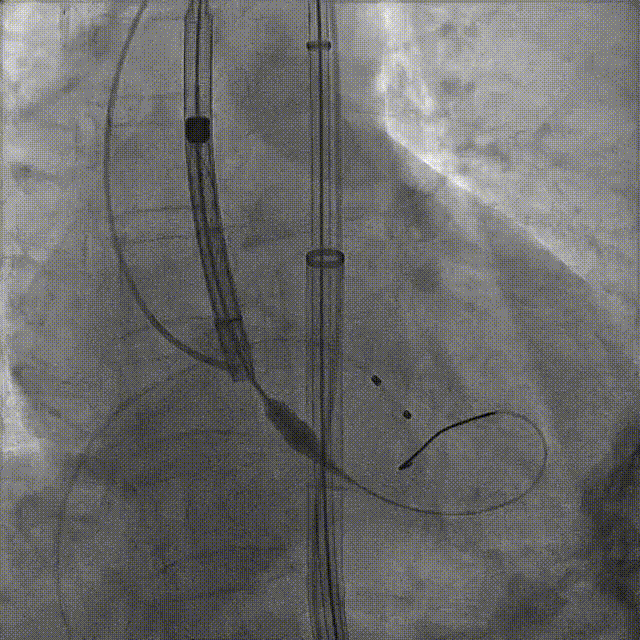

宋光远教授 首都医科大学附属北京安贞医院(点击查看专家详细简历) 技术革新不止,创新求索不辍:一切从患者出发,不断追求创新是内心的坚定。当年‘ALL IN ONE’的探索,正是怀揣着这份初心 —— 通过整合器械与操作,将入路创伤缩至最小,让患者在微创中更快康复,这是技术对患者的温柔承诺。而术中脑保护,是我们为安全筑牢的另一道防线。 此次预装干瓣的临床应用,让我们直面瓣膜“耐久性“临床困境,期待创新技术助力全生命周期管理! 病例概览 患者病史 患者因 “劳力性呼吸困难半年余,加重 20 天” 入院。高血压病史 20 年,最高血压 160/110mmHg;高脂血症病史;反流性食管炎。 超声提示:主动脉流速 Vmax 4.66 m/s,平均压差 53mmHg,左室射血分数(LVEF)40%; 超声诊断:主动脉瓣狭窄(重度)、主动脉瓣反流(轻中度)、二尖瓣狭窄(轻度)、二尖瓣反流(轻度)、三尖瓣反流(轻中度)、左房增大,左室肥厚。 术前CT 瓣环(Annulus)直径:22.9mm,左室流出道(LVOT)直径:周长径 23.8mm;总钙化负荷1239mm³(HU850),钙化集中于无冠窦,且蔓延至 LVOT,呈重度钙化表现;LVOT-Annulus 呈微直筒型,瓣上限制较重。左冠脉开口高度略低,瓣叶不长、窦部空间较大,结合钙化分部情况,预估双侧冠脉遮挡风险较低。室间隔膜部较短(2.4mm)有一定PPI风险,心室大小可,心脏角度64°,升主长度短于胶囊腔长度,同轴有一定困难。 · 造影角度及入路情况:主动脉弓角度可,但降主动脉折曲明显,双侧髂股动脉存在粥样硬化。 手术策略 采用 “极简式” 手术方案:18/20mm 球囊预扩张,植入金仕生物 Prostyle-A 预装干瓣(AV 26),配合长鞘,同时植入脑保护装置以降低卒中风险。 手术过程 球囊预扩:18号球囊预扩 输送系统顺利过弓跨瓣: 瓣膜植入:工作位观察位置适宜,完成植入。 术后即刻:术后造影显示瓣膜位置佳 入路与血管:撤出大鞘后检查,降主动脉仍存在较大弯折;入路闭合良好,无明显出血或血管并发症。 Prostyle A®预装干瓣——助力临床最优化解决方案: √ Mircro-EX™专利抗钙化技术:极简式预装干瓣,不使用戊二醛浸泡,减少钙化成因,干态存储的瓣膜术中无需清洗瓣膜,减少组装步骤,缩短手术时间,尤其适合复杂病例中的高效操作; √ 平衡的径向支撑力:重度钙化的患者,形态展开良好,在横位心等复杂情况下实现稳定锚定及释放; 专家简介 苑飞 首都医科大学附属北京安贞医院(点击查看专家详细简历) 姚晶 首都医科大学附属北京安贞医院(点击查看专家详细简历) · END ·